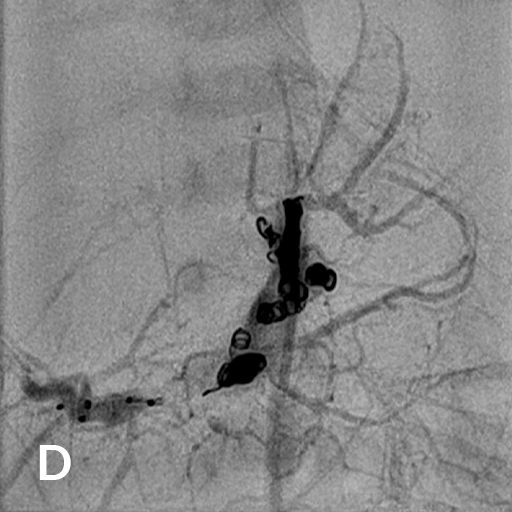

Reifes Neugeborenes mit Hepatomegalie und Herzinsuffizienz. Das MRT der Leber (A) zeigte ein ausgedehntes kongenitales Hämangiom mit normalem Lebergewebe in den Randbereichen vor allem links. Deutlich gestaute Lebervenen (B) infolge der Rechtsherzbelastung. Die Kontrastmittelinjektion die Arteria hepatica dextra (C) zeigt mehrere arterielle Feeder mit rascher Parenchympassage. Nach interventionellem Verschluss mittels 3 Vascular Plugs und insgesamt 28 Volumen-Coils deutliche Reduktion des Shunt-Flusses im rechten Leberlappen mit noch verbleibenden Hämangiomanteilen links (D).

Wissenschaftliche Abbildung Leberhämangiom